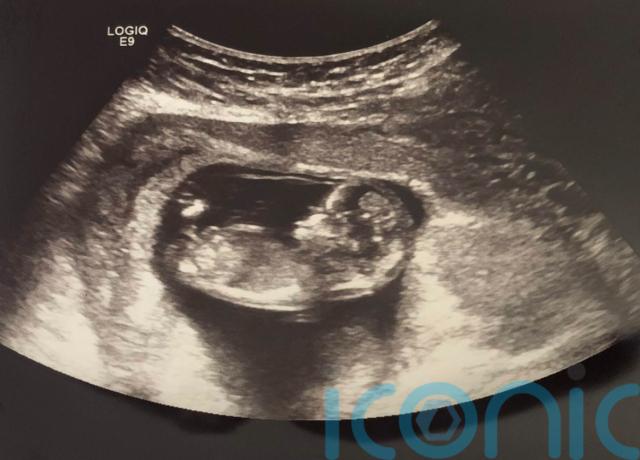

A young mother who has been pregnant 11 times and lost seven babies in the space of seven years has said there are ways to find “comfort amidst the storm”.

Carmen Grover, a 33-year-old registered nurse who lives in Ontario, Canada, lost four babies, which caused “such heartbreak”, before having her first son, Case, in December 2017.

She gave birth to her daughter, Maelie, in April 2019, but experienced two more losses after this, including her baby, Jude, who died shortly after birth in August 2020 and was so small that doll’s clothes “fit him perfectly”.

After giving birth to her second daughter, Ayda, in July 2021, Carmen experienced her seventh loss but knew she wanted to “try one more time”, leading to Charlotte being born in February 2024.